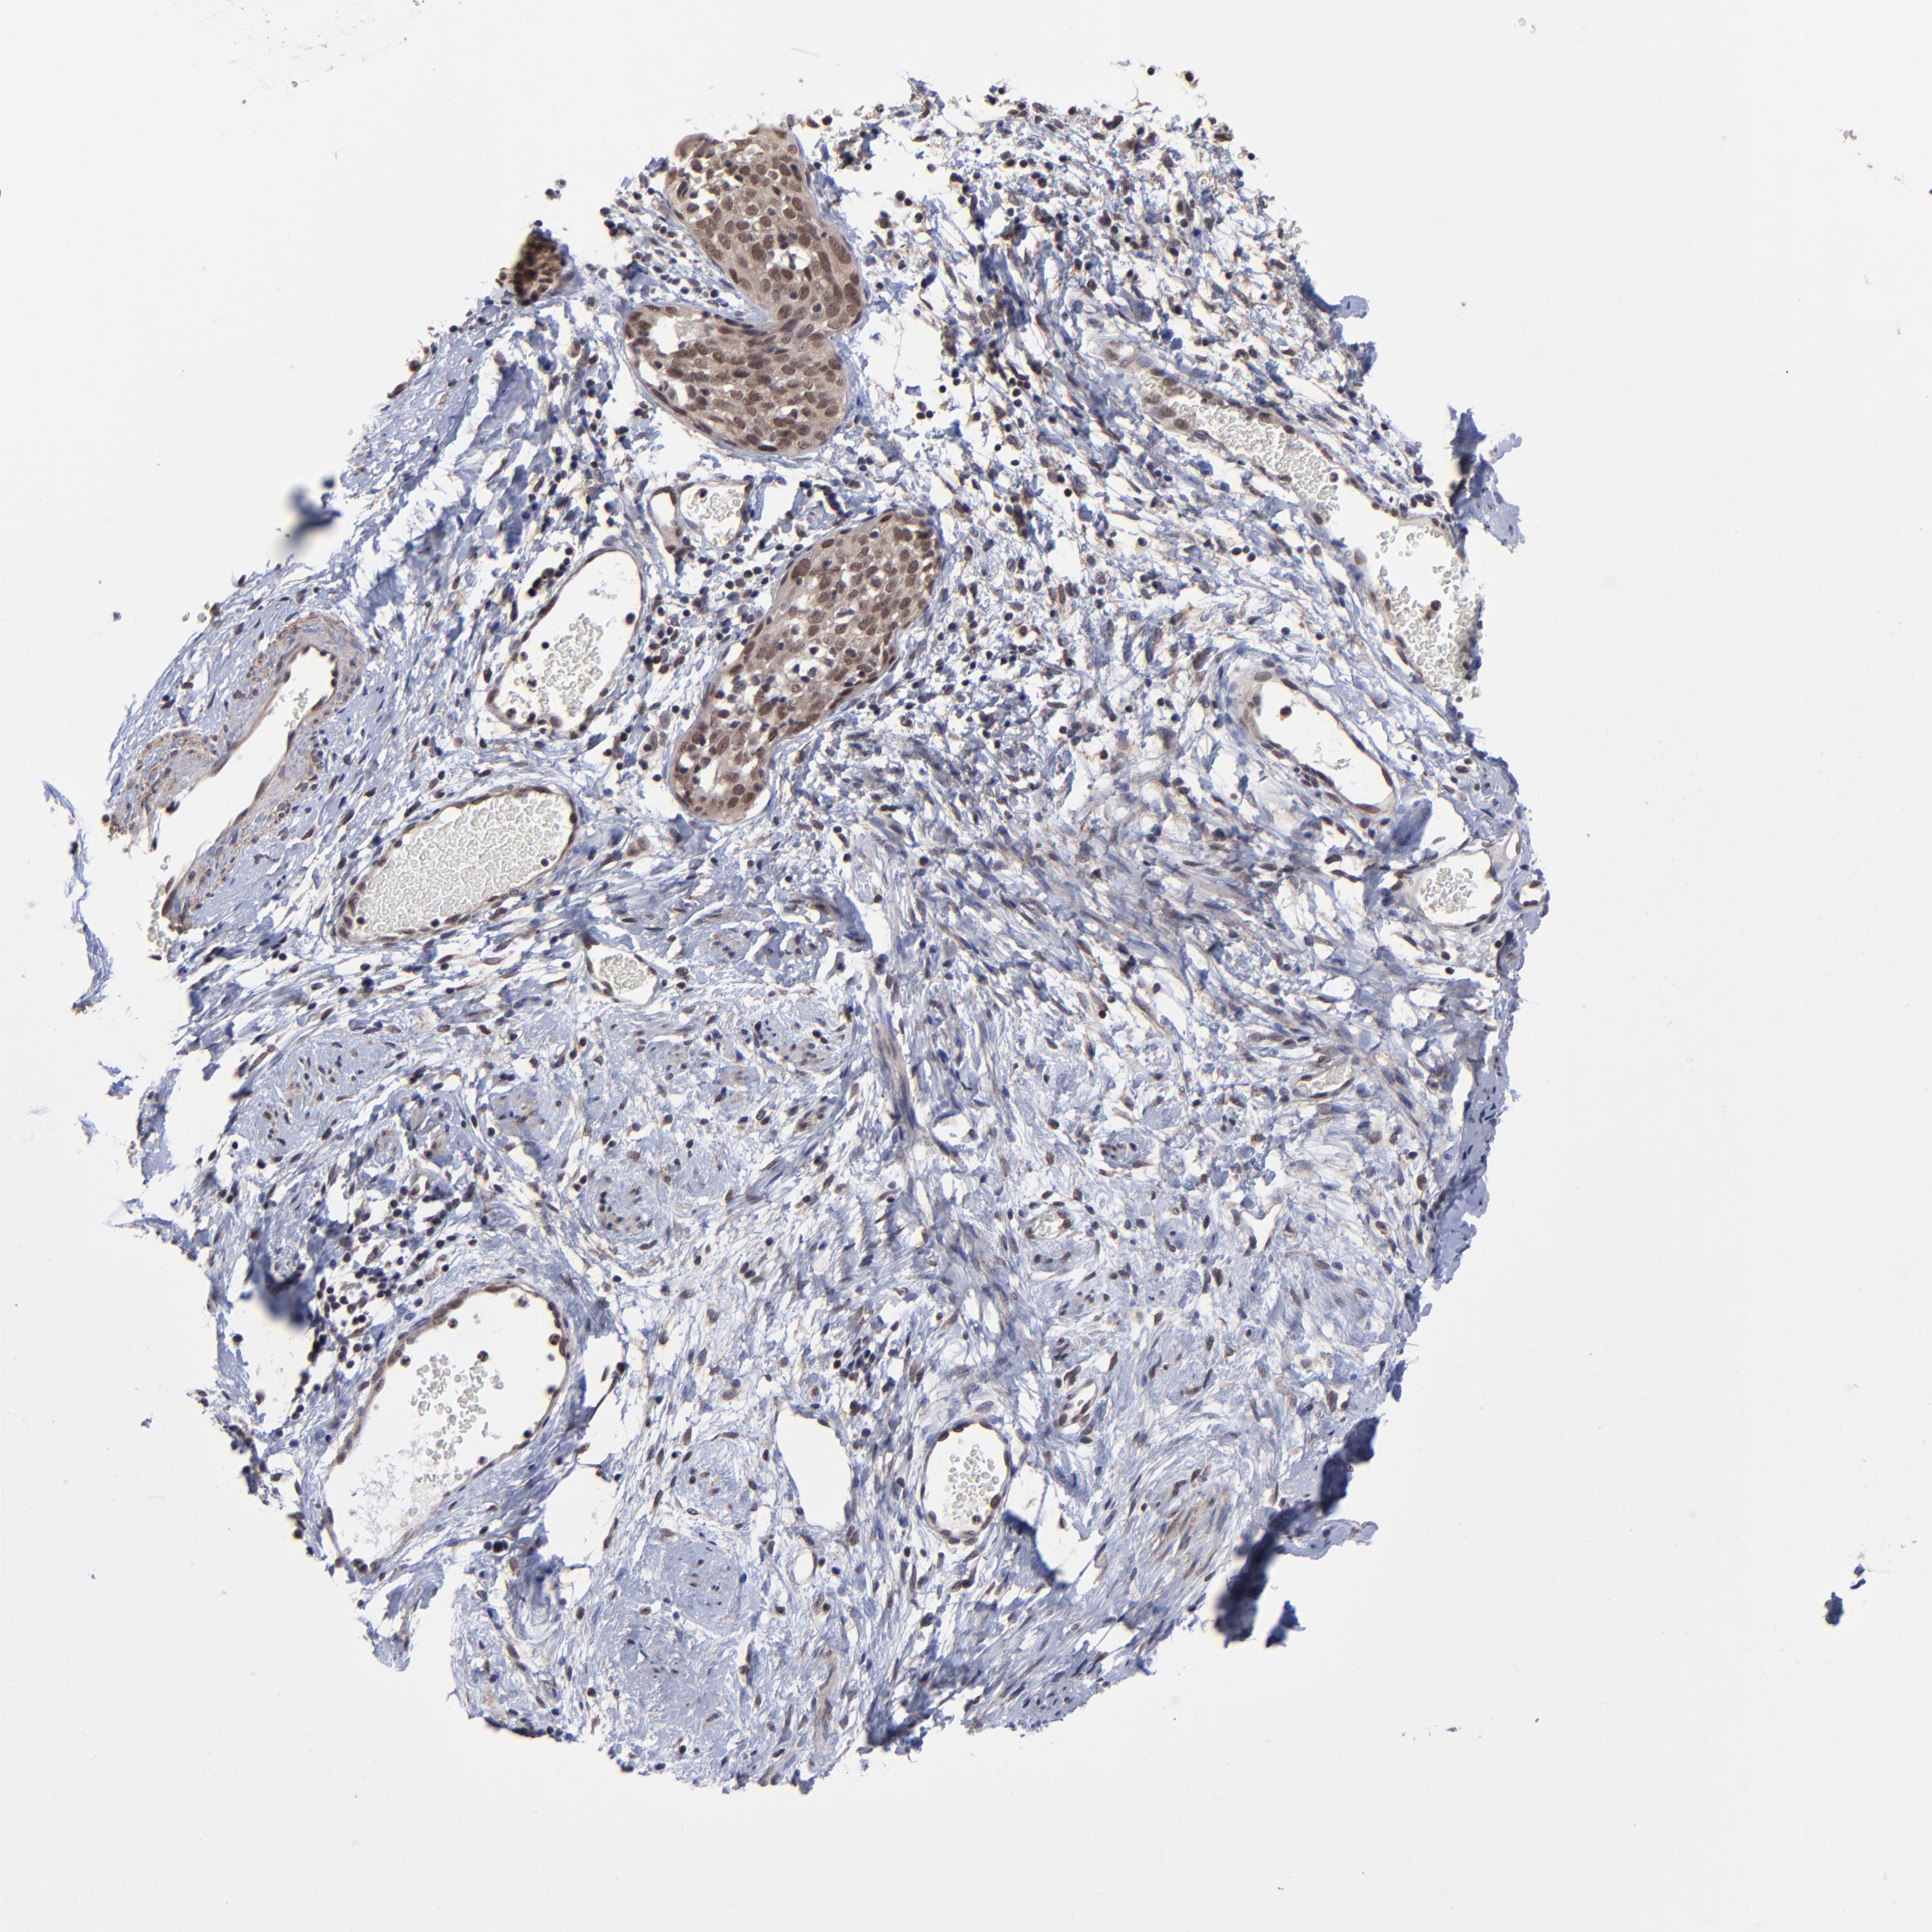

CERVICAL CANCER - Protein expressioni

A mouse-over function shows sample information and annotation data. Click on an image to view it in a full screen mode. Samples can be filtered based on level of antibody staining by selecting one or several of the following categories: high, medium, low and not detected. The assay and annotation is described here.

Note that samples used for immunohistochemistry by the Human Protein Atlas do not correspond to samples in the TCGA dataset.

Antibody stainingi

Antibody staining in the annotated cell types in the current human tissue is reported as not detected, low, medium, or high, based on conventional immunohistochemistry profiling in selected tissues. This score is based on the combination of the staining intensity and fraction of stained cells.

Each image is clickable and will lead to virtual microscopy that enables deeper exploration of all samples and also displays staining intensity scores, fraction scores and subcellular localization as well as patient and tissue information for each sample.

Antibody HPA003152

Antibody HPA003274

Staining

High

Medium

Low

Not detected

Intensity

Strong

Moderate

Weak

Negative

Quantity

>75%

75%-25%

<25%

None

Location

Nuclear

Cytoplasmic/membranous

Cytoplasmic/membranous,nuclear

Squamous cell carcinoma, NOS

Adenocarcinoma, NOS